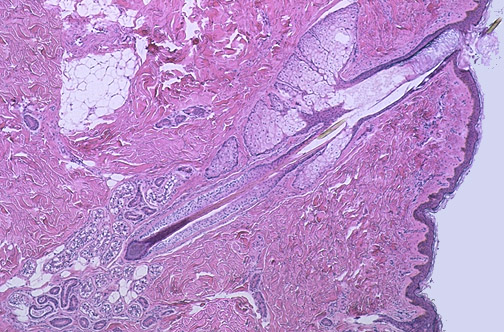

| Here are normal adnexal structures of the skin, which determine so much of how people on earth spend their time and money, as well as social interactions. A hair follicle is seen at the center, with sebaceous glands above and sweat glands and ducts near the base of the hair follicle. |